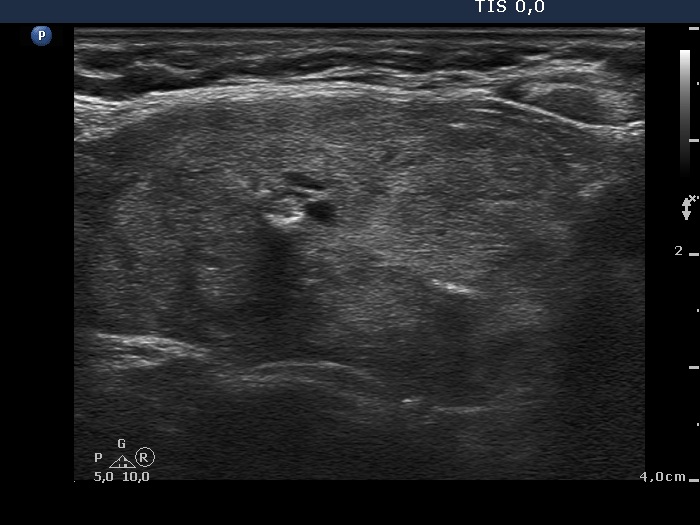

Lower part of the right lobe

|

This nodule has multiple coarse calcifications and proliferation of a connective tissue (arrowheads and arrows).